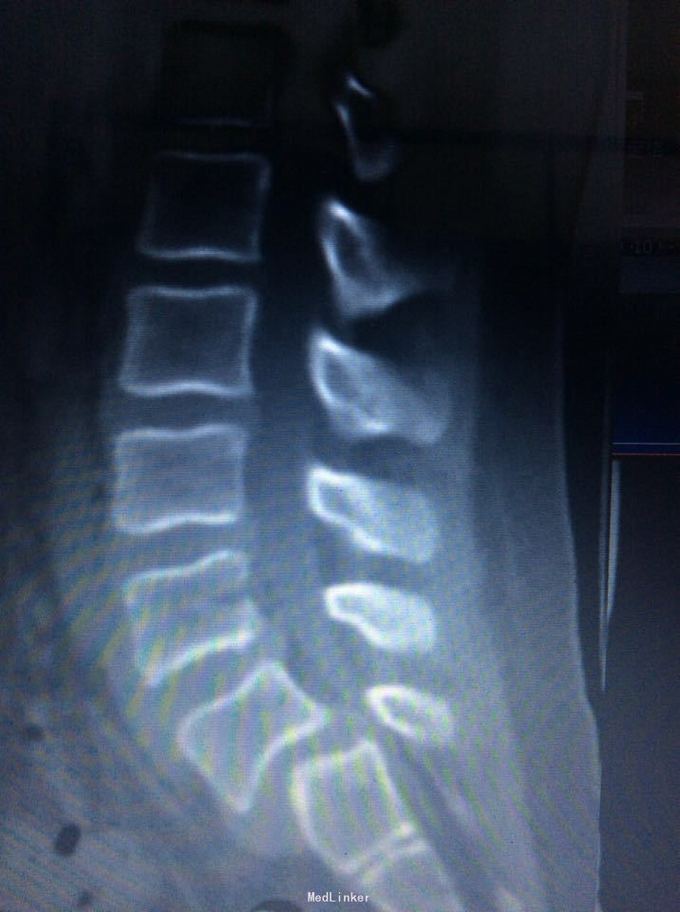

腰椎滑脱

椎体滑脱

9岁,腰痛一年

术前joa 评分17分

腰5椎体滑脱ii度 后路椎弓根钉椎间自体髂骨融合